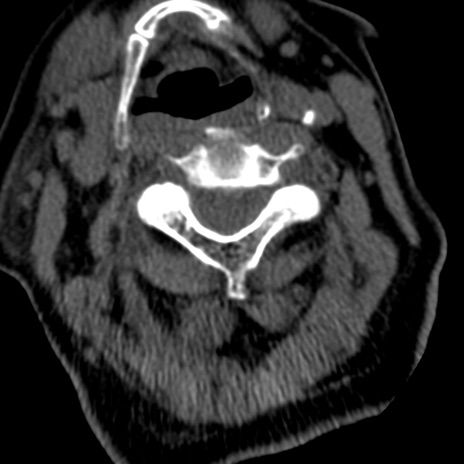

症例50 頚椎CT(横断像)

冠状断像